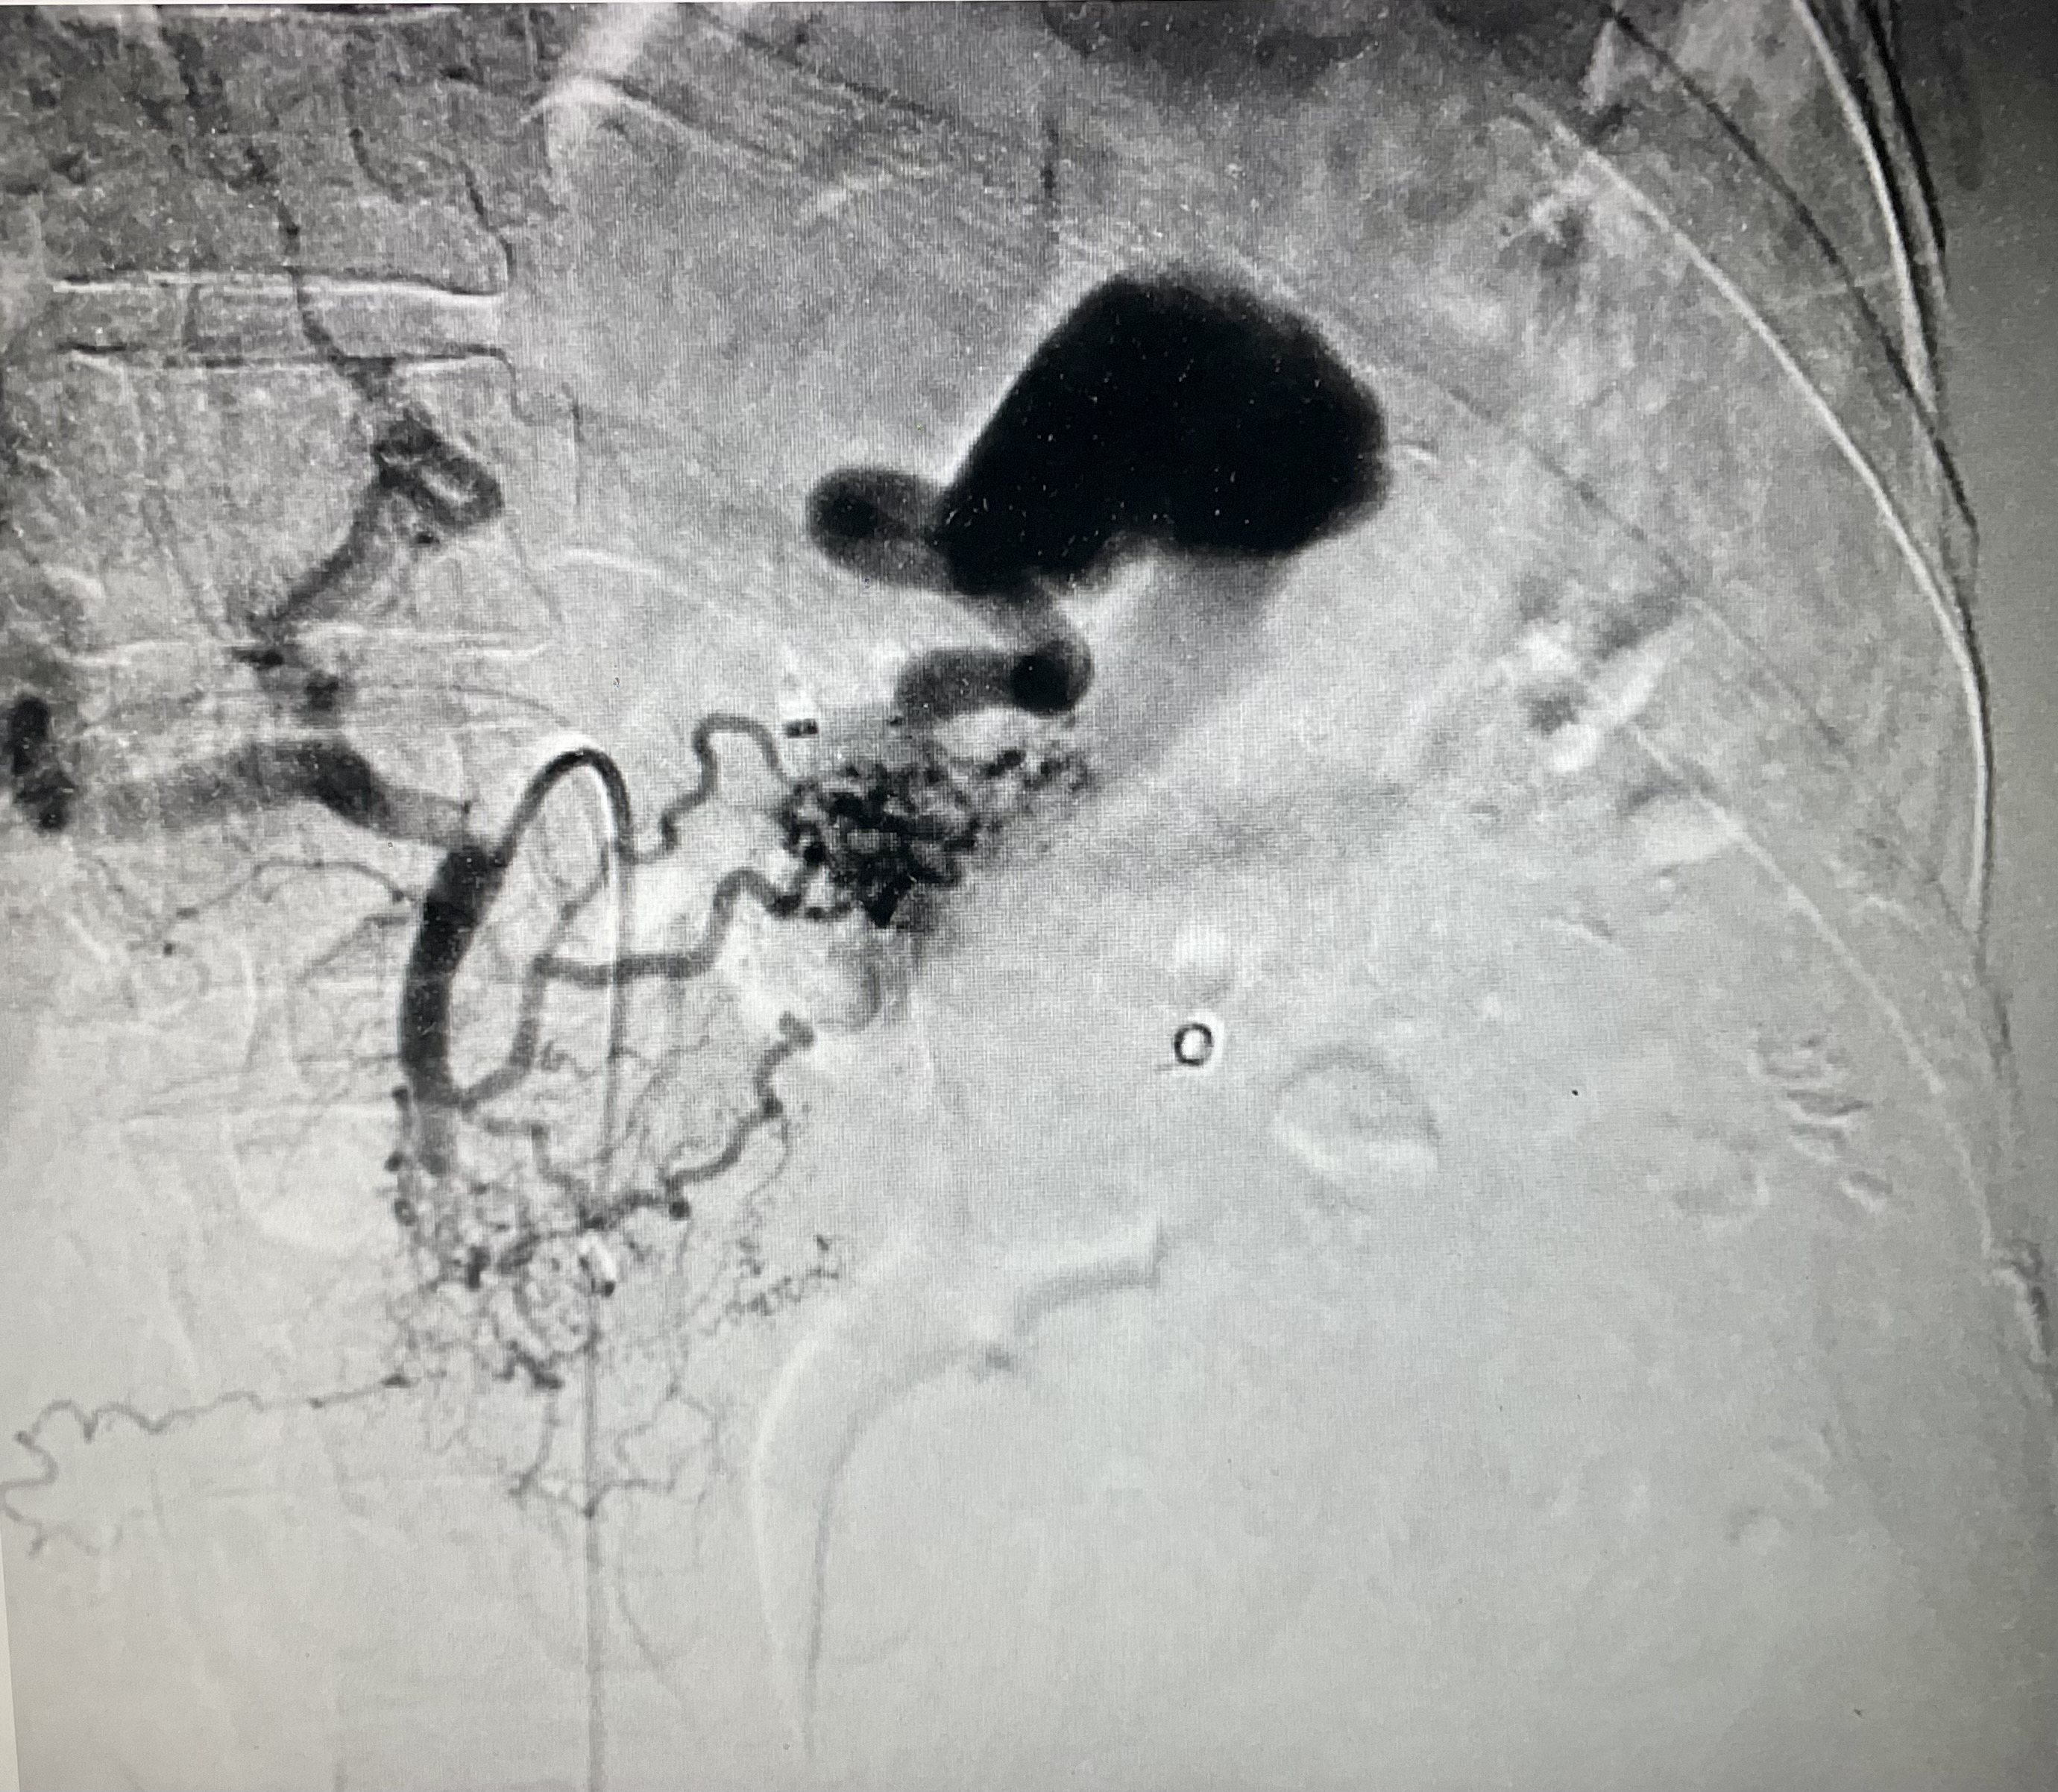

2. Целиакография. Определяются коллатерали от левой желудочной артерии к дистальной части селезеночной артерии | |